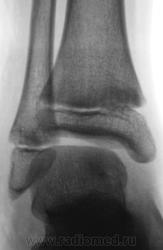

Травма. Пациент направлен хирургом на рентгенографию голеностопного сустава. Произведено стандартное исследование.

Уважаемый Валентин Львович! А что в жалобах, анамнезе? В переднемедиальной зоне дист. метафиза б/берцовой кости субхондрально под зоной роста участок уплотнения к/структуры, не отграниченный от неизмененной костн. ткани. Возможно, это импрессионный перелом? или остеонекроз? Смущает небольшой очаг аналогичной структуры в таранной кости под медиальным валом блока.

Клиника перелома. Травма - за 4 часа до исследования.

Согласен с коллегой helenmar по поводу перелома по типу импрессии, а ещё подвывих стопы в г/стопном суставе.

У взрослого такие соотношения в суставе назову супинационным подвывихом, хотя прямая проекция не оптимальна для такого заключения, боковая вовсе косая.